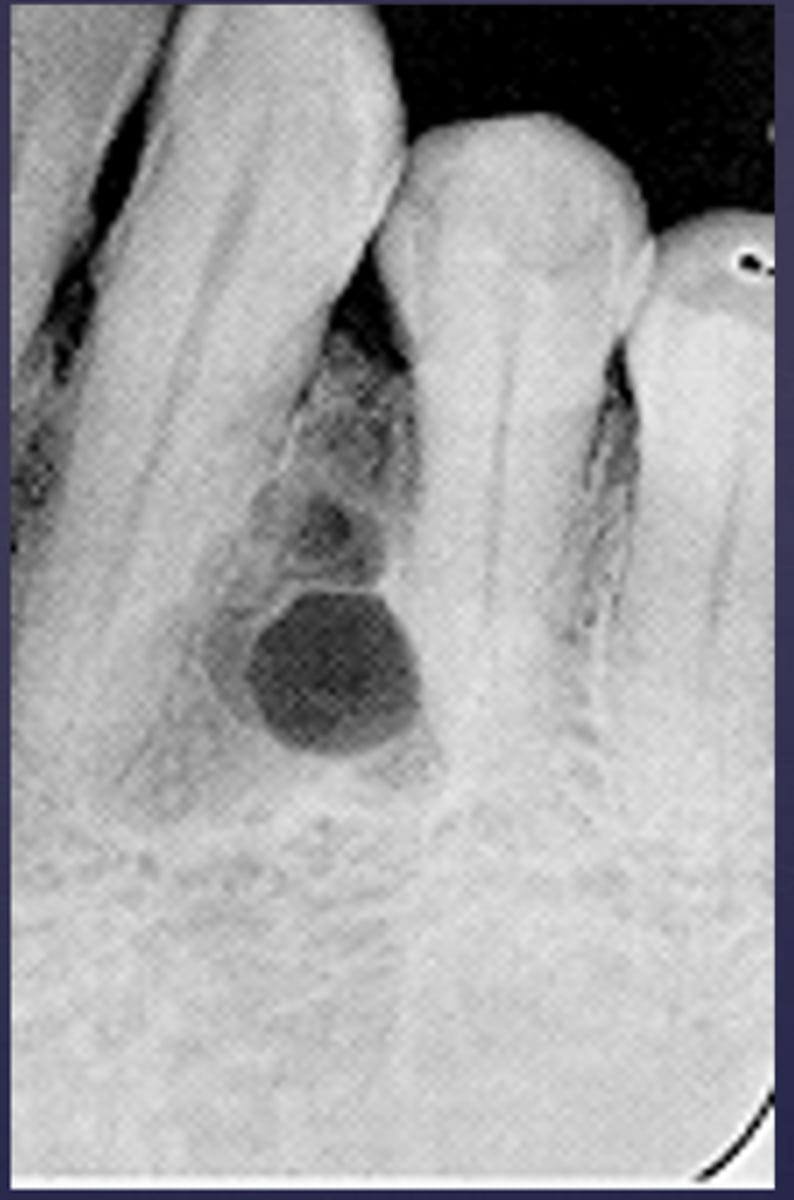

how would you describe this lesion?

A. well-defined, periapical radiolucent lesion associated with #24 and 25

B. ill-defined, periapical radiolucent lesion associated with #24 and 25

C. well- defined, multilocular periapical lesion associated with tooth number 24 and 25

D. mixed density, periapical lesion associated with teeth number 24 and 25

- Also note loss of apical lamina dura of 24, 25

What category would this lesion be part of?

Dysplasia

What would be a differential diagnosis for this lesion?

PCOD (stage 1)